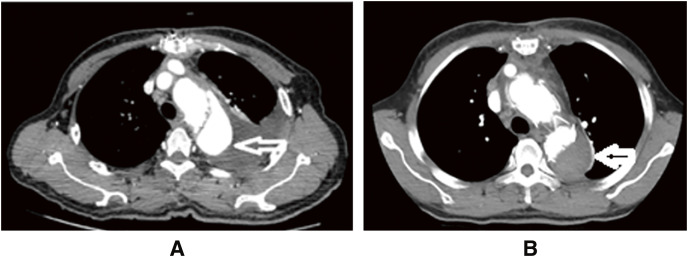

Objectives: We evaluate the preliminary and intermediate-term results of Viet Duc modification of the frozen elephant trunk (FET) technique. Methods: During December 2019 and May 2023, 47 patients underwent surgery using our modification of the FET at Viet Duc University Hospital. The mean age of the patients was 56.8 years (±9.4, range 31-72). In all, 34 (72.3%) of the patients were men. Results: There were 5 (10.6%) perioperative deaths. The duration of cardiopulmonary bypass, cross-clamping, circulatory arrest, and total operation were 165 (±49.1 range 94-330), 100 (±37, range 46-205), 32.6 (±8, range 20-58), and 366 (±60.6, range 270-540) minutes, respectively. In complications, tracheotomy, temporal hemodialysis, cerebral shock, and type 1A endoleak were noted in 3 (6.4%), 4 (8.5%), 4 (8.5%), and 3 (6.4%) patients, respectively. The mean follow-up time was 25.8 months (±11.7, range 3-42). One case was dead in the follow-up period. Three patients (6.3%) had successful reoperation for type 1A endoleak, and 4 patients (8.5%) underwent a second intervention. One (2.1%) patient had a second intervention and an infrarenal abdominal aortic replacement. Conclusions: Our modification of the FET technique was feasible, effective, and safe, with good early and intermediate-term outcomes.